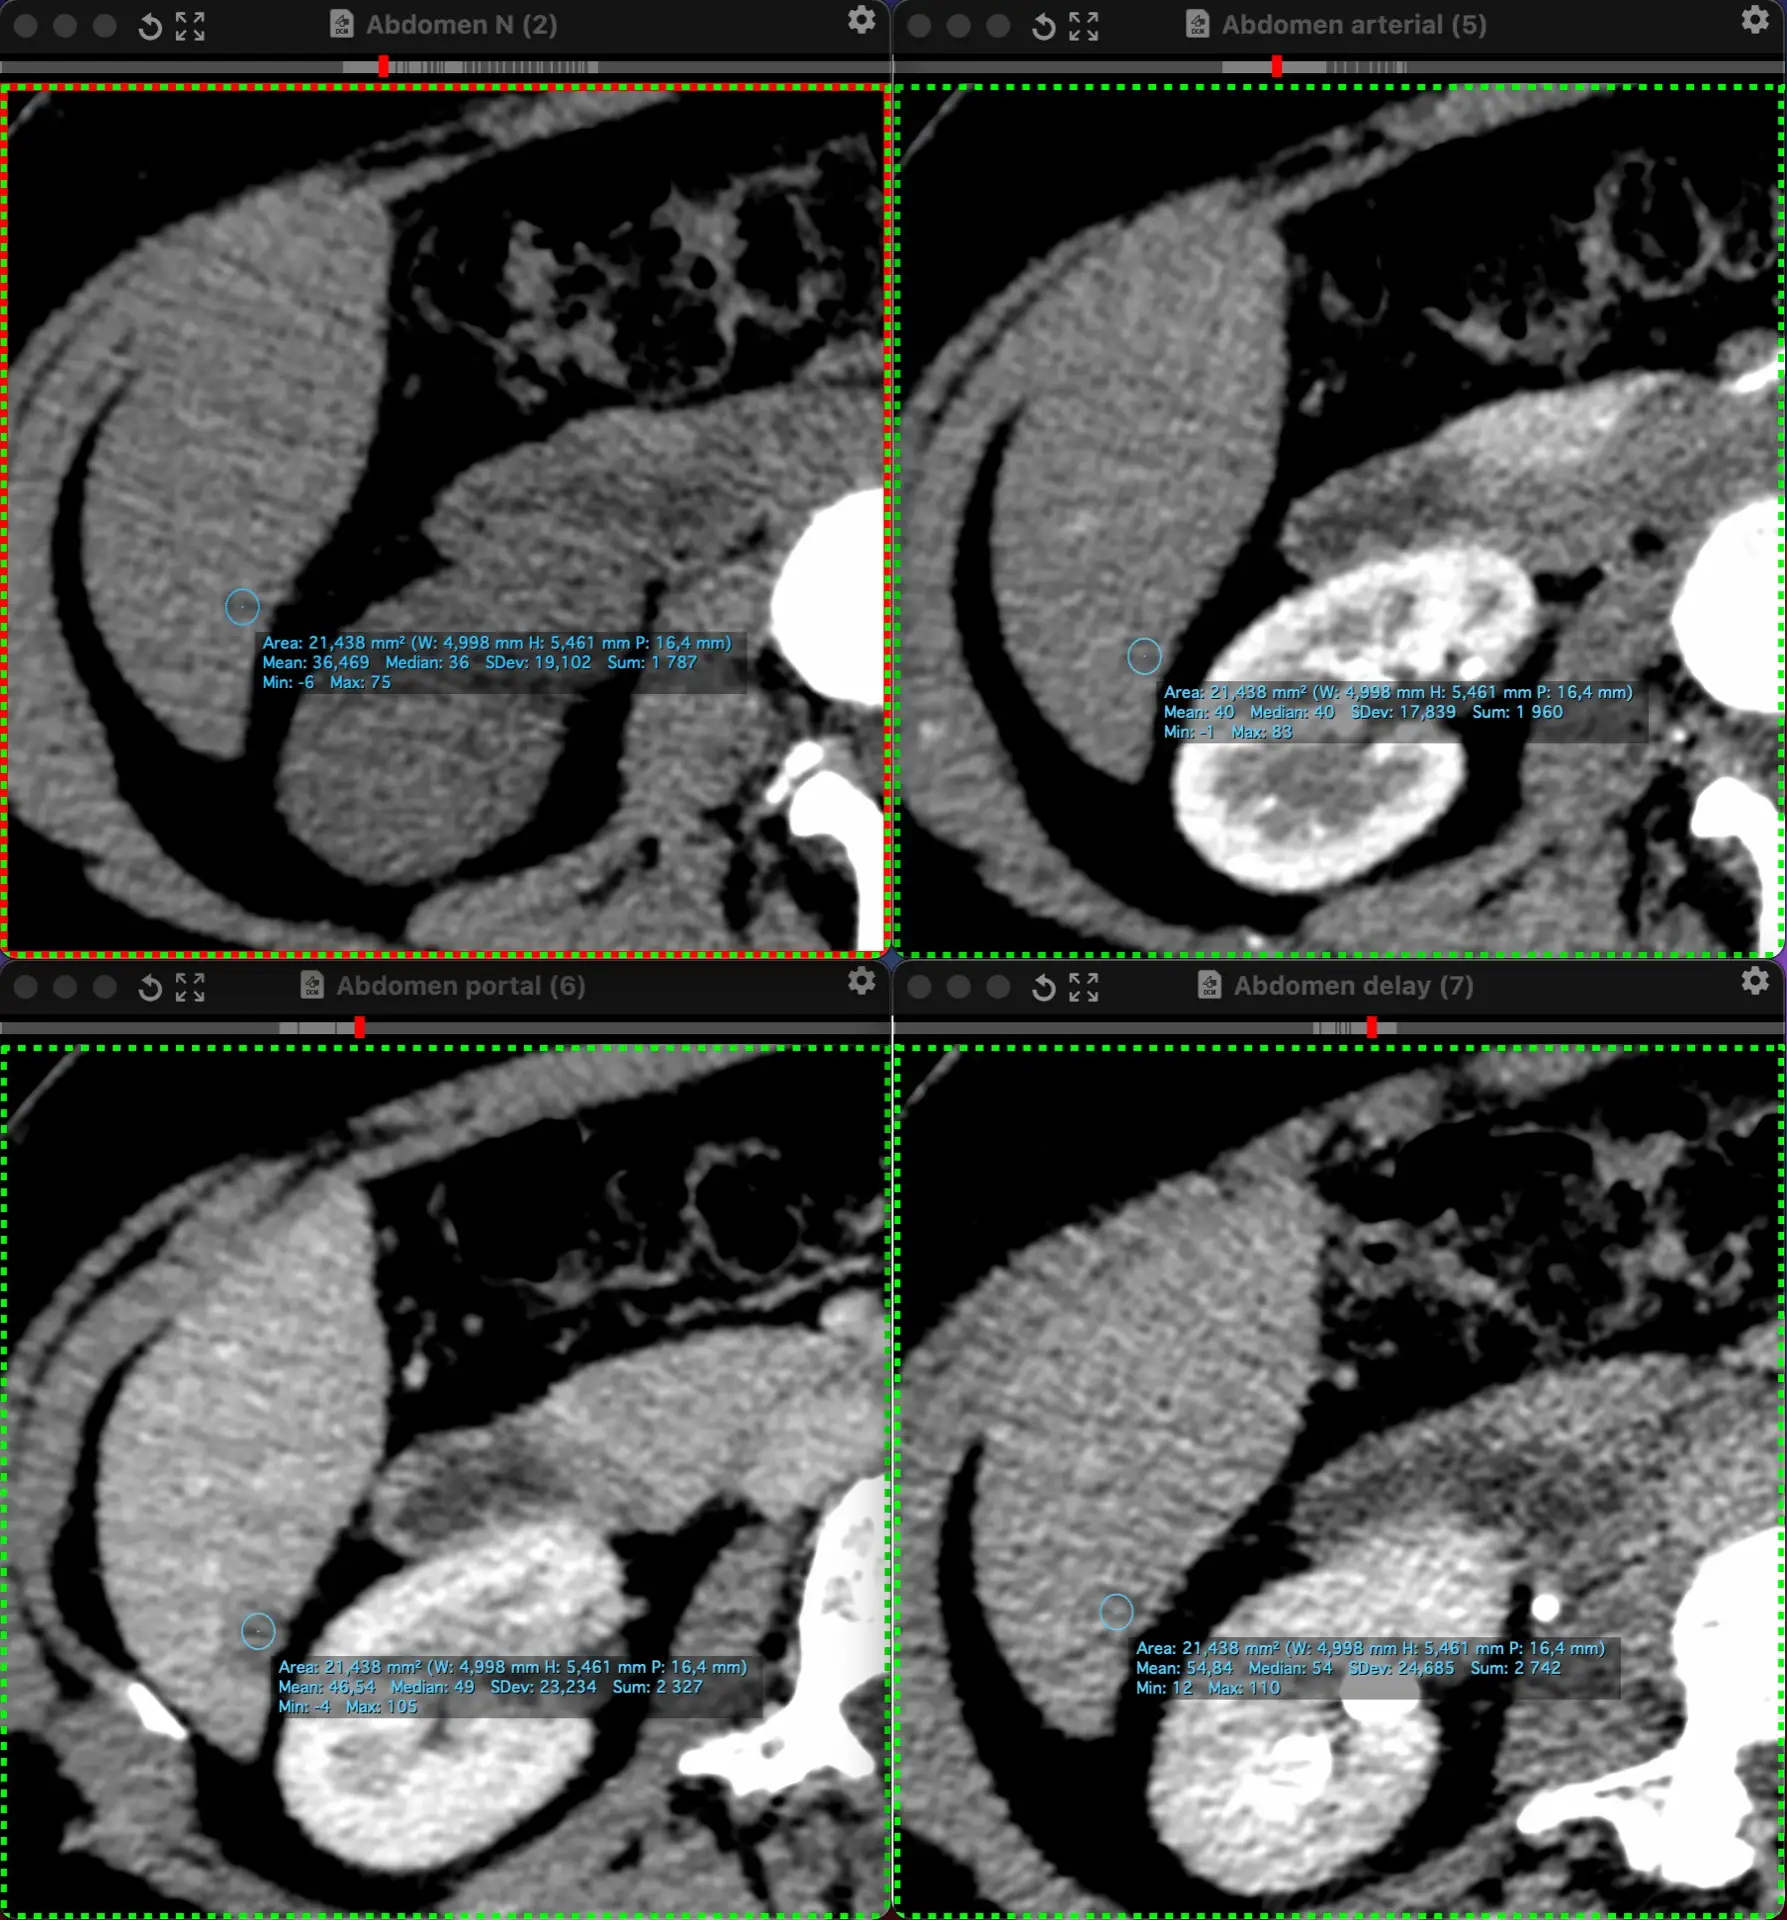

ЖЕНЩИНА 38 лет, фокальное изменение печени выявлено на УЗИ.

Повторные #КТ (с разницей в 2,5 месяца) без динамики. Имеется медленное, постепенное, слабоинтенсивное накопление контраста от периферии к центру.

На #МРТ - очень высокий сигнал на Т2, низкий на Т1, «лучистые» контуры. Истинное ограничение диффузии (ADC=460±109х10-6 кв.мм/с). Накопление контраста такое же, но на МРТ лучше видны краевое узелков накопление в артериальную фазу, тотального контрастирования нет даже на отсроченной фазе (через 5 минут).

Картина характерна: это гиалинизированная/ #склерозированнаягемангиома. Характерное стяжение контура является свидетельством склерозирования: уменьшения объёма, «рубцевания».

Гемангиомы с суженными кавернозными пространствами из-за склероза имеют большее количество более толстых и неровных перегородок, которые могут препятствовать диффузии молекул, что приводит к снижению значений ADC.

Склерозированные гемангиомы печени — это редкие доброкачественные поражения, которые часто трудно отличить от злокачественных, ибо они не имеют типичных для кавернозных гемангиом признаков.

Но! Часть признаков все равно сохраняются:

1. Значительный гиперсигнал на т2

2. Резкие, хоть и неровные, контуры

3. Центрипетальное, и иногда с приставочными узелками накопления контраста на артериальной фазе, контрастирование, пусть и неполное.

4. Стабильность в динамике